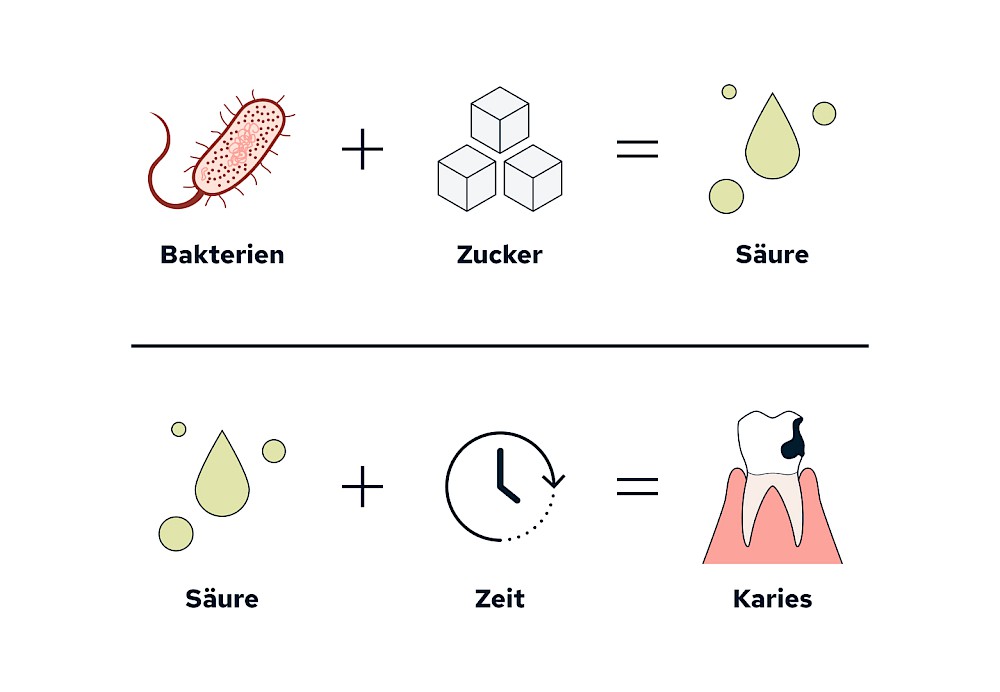

Entstehung

Karies ist ein Demineralisationsprozess der Zähne, bei dem bestimmte Bakterien Zucker zu Säuren verstoffwechseln und diese Säuren über die Zeit die mineralische Zahnoberläche anlösen.

Bestimmte Bakterien (Mutans-Streptokokken und Laktobazillen) in der Plaque bzw. dem Biofilm auf der Zahnoberfläche benötigen Zucker (z.B. aus der Nahrung) für ihren Stoffwechsel. Dabei entstehen Säuren. Diese Säuren werden von den Bakterien an die Umgebung abgegeben. Über die Zeit lösen die Säuren die mineralischen Zahnoberflächen auf (Demineralisierung). Diesen Prozess bezeichnet man als Karies.